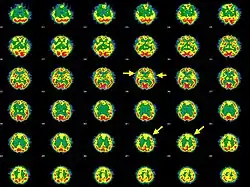

| Brain SPECT transaxial images of a patient afflicted with Hashimoto's encephalopathy showing cerebral hypoperfusion in the left frontal lobe and in both temporal lobes (arrows). | |

- Single photon emission computed tomography shows focal and global hypoperfusion (75% of cases)